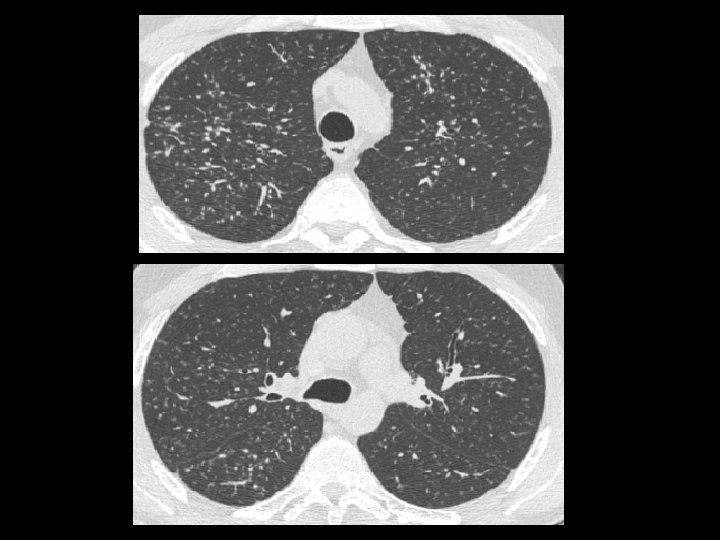

En ambos hemitórax se observan múltiples imágenes nodulillares de escasos milímetros de distribución difusa, predominando en los lóbulos superiores, de localización aleatoria En topografía del LM se observan aisladas prominencias bronquiales con sutiles cambios inflamatorios peribronquiales sin evidencia de consolidación. Pequeñas imágenes ganglionares a nivel supraclavicular en rango no adenopático. En topografía del espacio paratraqueal derecho y espacio subcarinal así como también a nivel hiliar bilateral se observan pequeñas imágenes ganglionares algunas con calcificaciones en su superficie de corte. Derrame pericárdico.

Imágenes características en tc: • Pequeños nódulos parenquimatosos distribuidos predominantemente en región peribroncovascular o en septos interlobulillares ( + frec ) • Engrosamiento septal interlobulillar(50%) • Adenopatías mediastinales (39%) • Engrosamiento paredes bronquiales (46%) • Opacidades en vidrio esmerilado (32%) • Patrón en panal de abeja (7%)

Pequeños nódulos peribroncovasculares y a lo largo de los septos interlobulares con una distribución perilinfática

Nódulos centrolobulillares y perilinfáticos Vidrio esmerilado

Opacidades nodulares, bronquiolectasias nódulos subpleurales